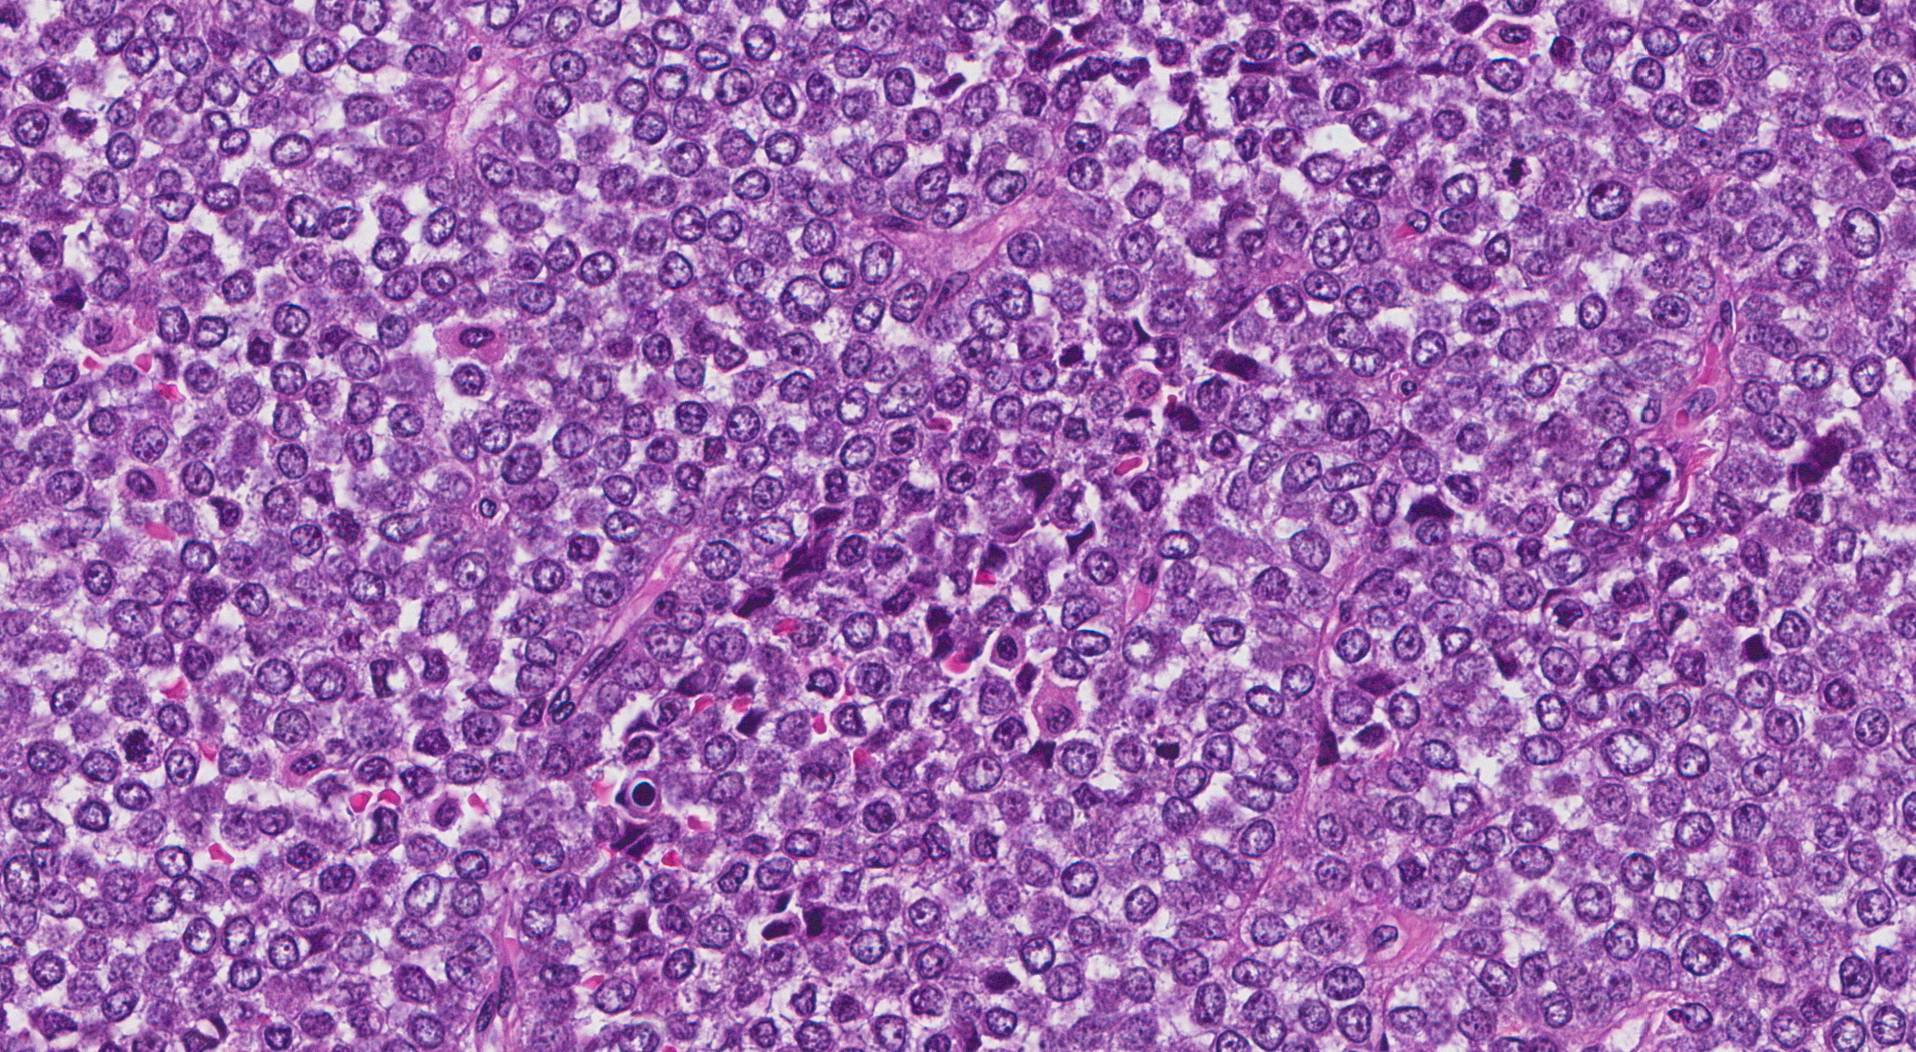

Diagnosticato presso l’Unità operativa complessa di Oncoematologia Pediatrica del Policlinico di Bari diretta dal dottor Nicola Santoro il primo caso pediatrico in Italia di “carcinoma NUT”. Il “carcinoma NUT” è un tumore eccezionalmente raro e a prognosi quasi invariabilmente infausta, con pochissimi casi descritti nel mondo.

Il paziente, un ragazzino di 13 anni della provincia di Bari, aveva una evidente tumefazione della parete toracica a sinistra. Dopo l’accurata caratterizzazione istologico-molecolare, cui si è giunti anche grazie alla collaborazione con la prof.ssa Rita Alaggio (direttrice del Servizio di Anatomia Patologia dell’Ospedale “Bambin Gesù” di Roma), il piccolo è stato sottoposto ad un intervento chirurgico multidisciplinare durato circa 10 ore.